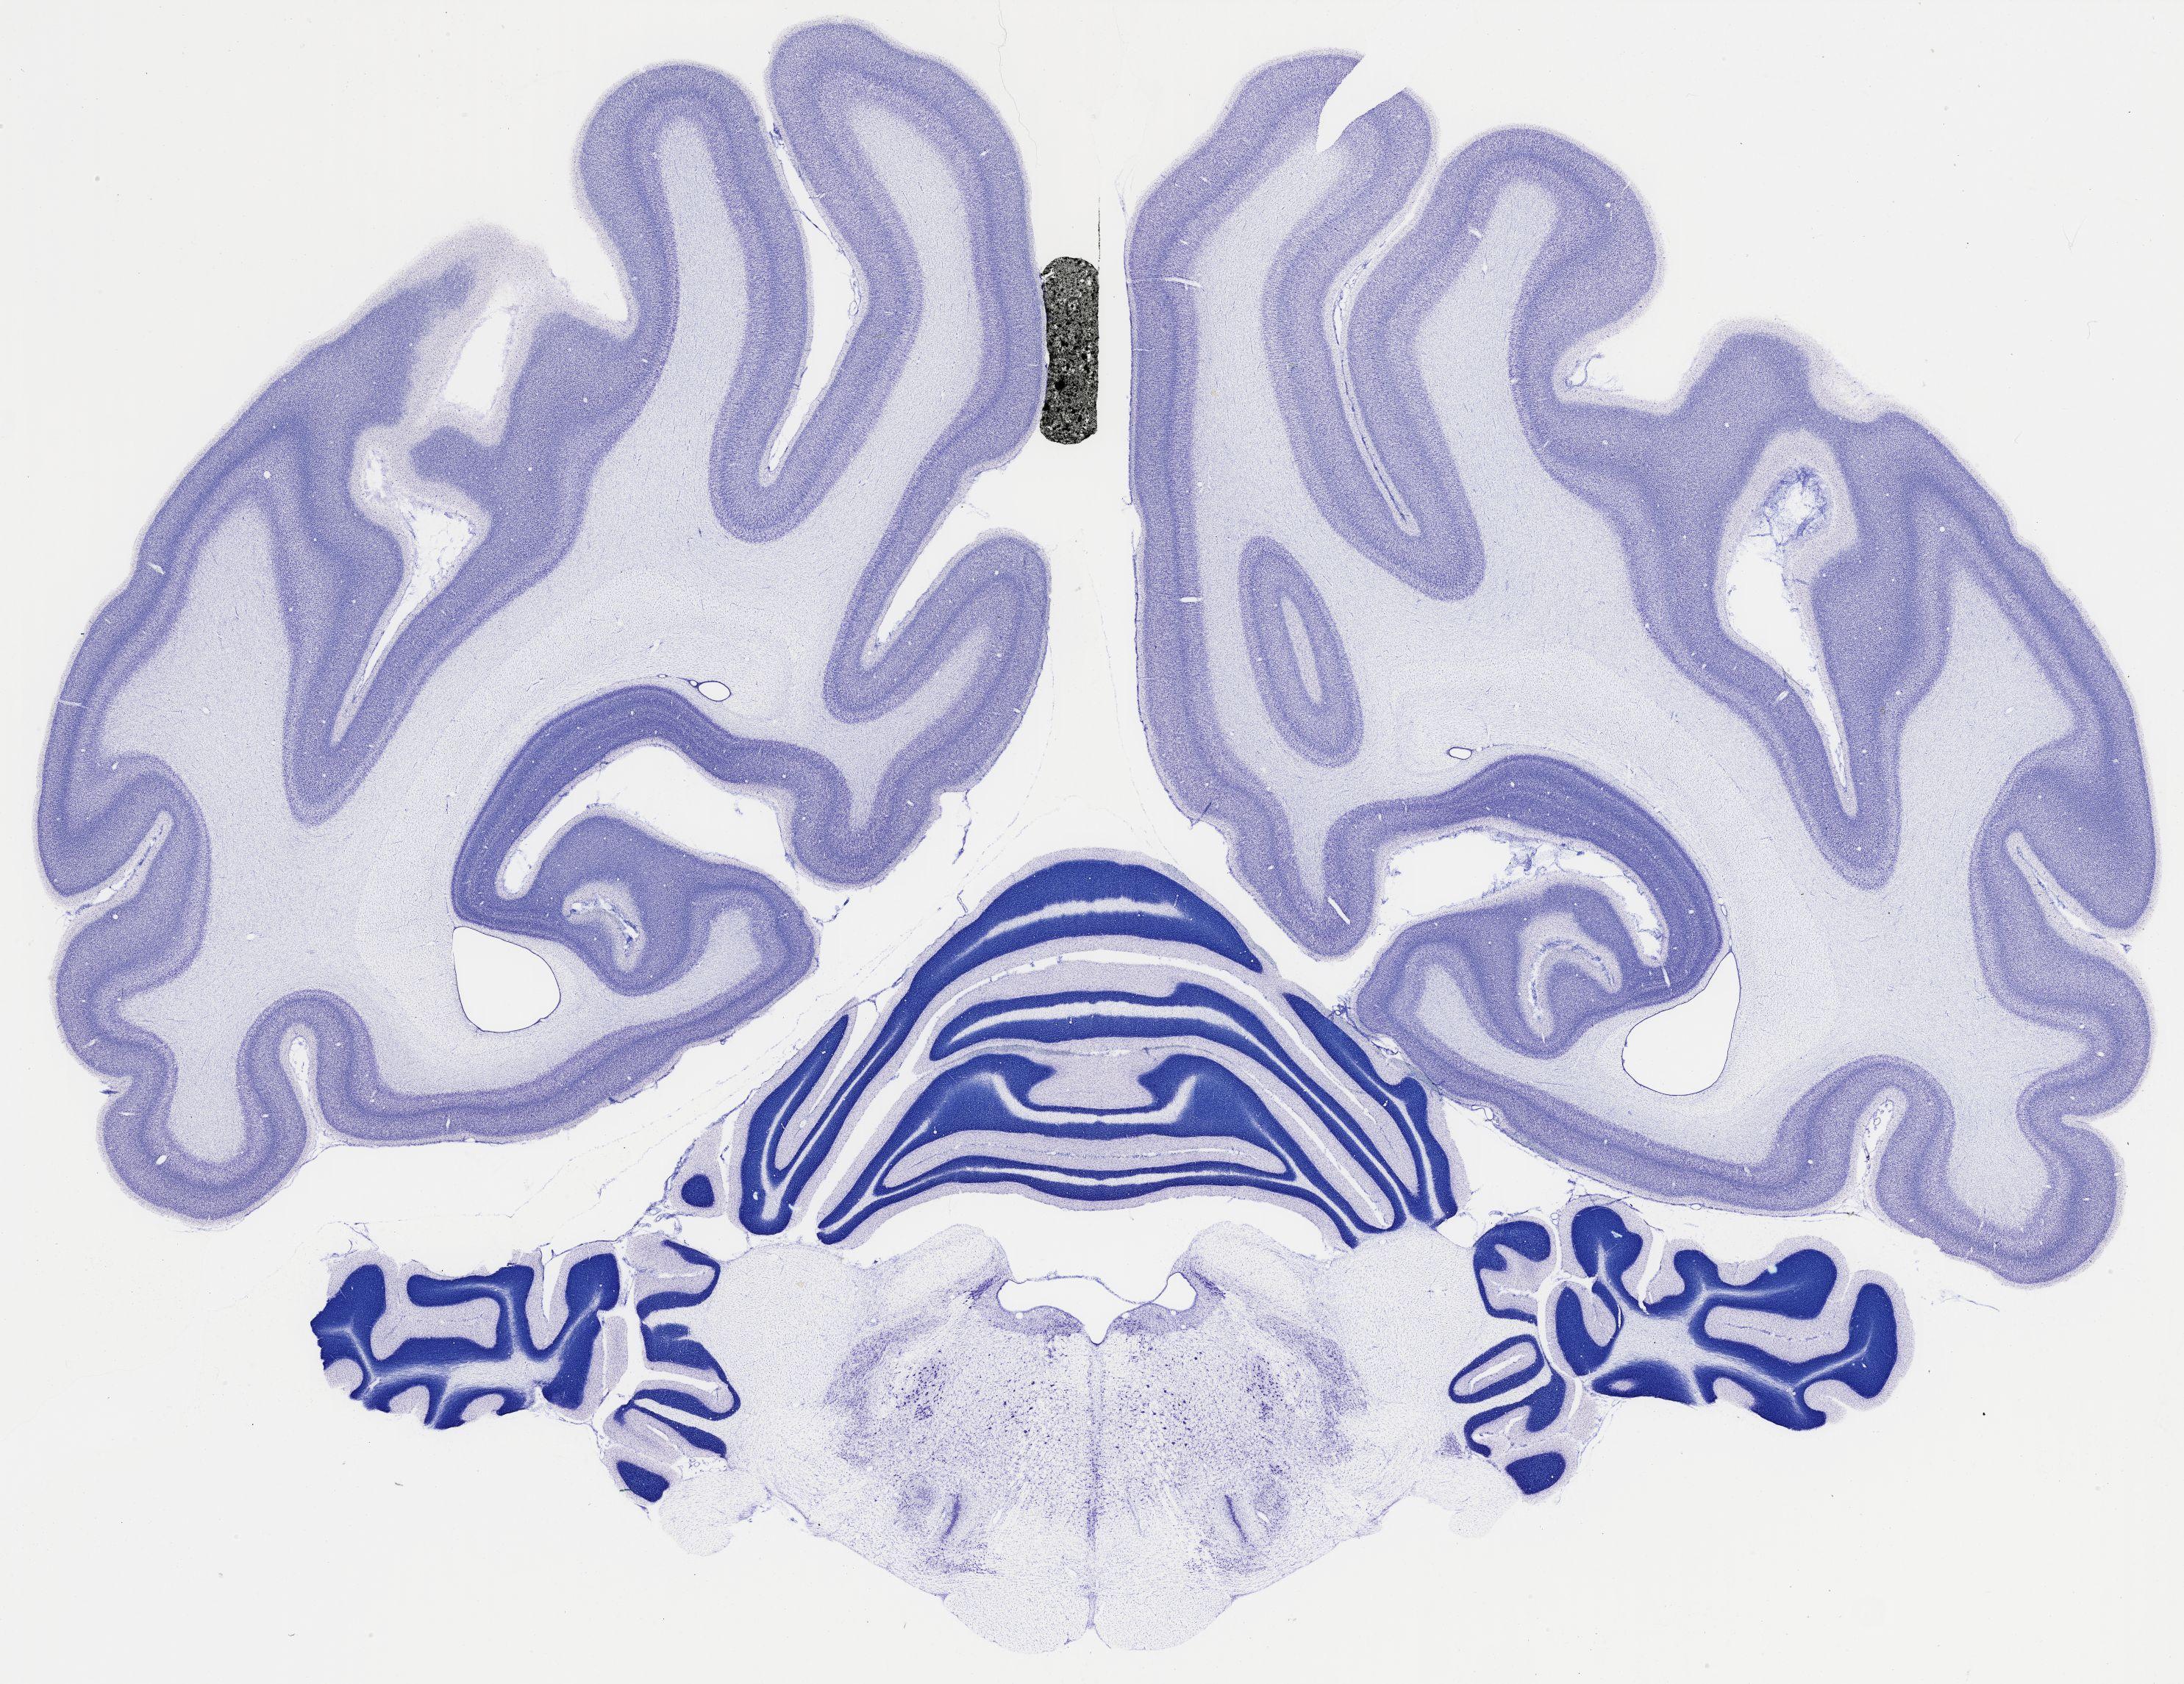

Datasets -> Chlorocebus Aethiops -> Nissl, coronal, histo, Whole-Brain, adult

[ Metadata ]   ·   Source: NeuroScience Associates

thumbnail

524